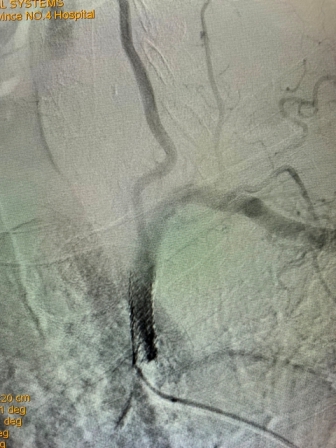

2021年8月5日,日韩无码 神经内科神经介入专家团队成功完成首例锁骨下动脉再通介入术

(术前造影) (术后再通造影)